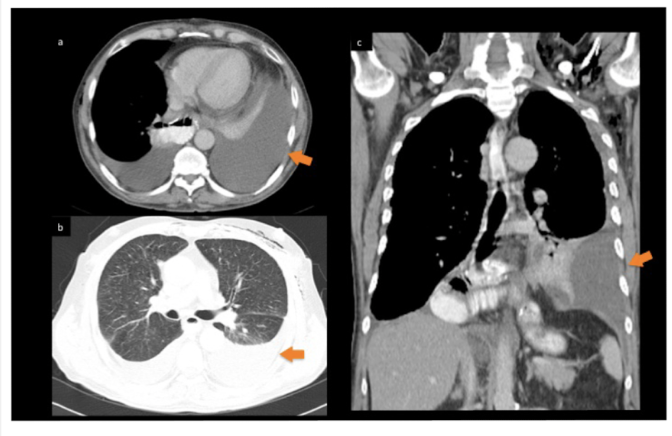

What is the protocol + pathology?

• CTPA

• There is max opacification within the pulmonary arteries therefore contrast was used and it’s in an EARLY arterial phase.

• Path = pulmonary embolism with an occlusion in the left pulmonary artery

• Filling defect characterised by hypodense streak within the left pulmonary artery.

• Coronal MIP = highest attenuation values within the voxel selected